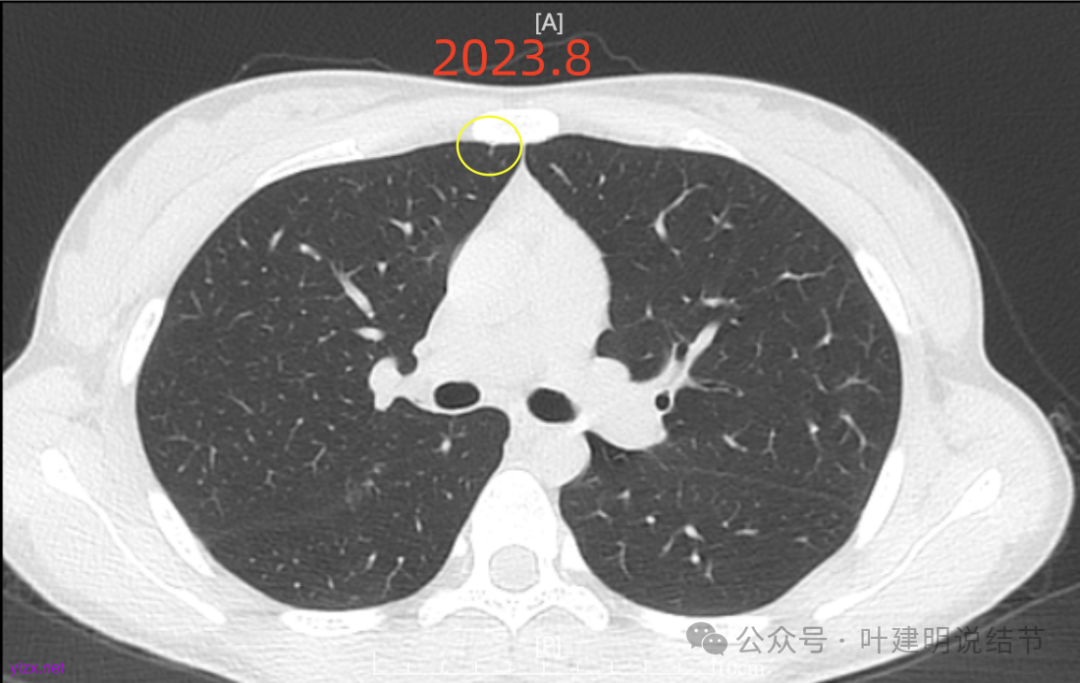

再来看风险最大的病灶6的连续层面:

血管从旁过,没有受结节影响。